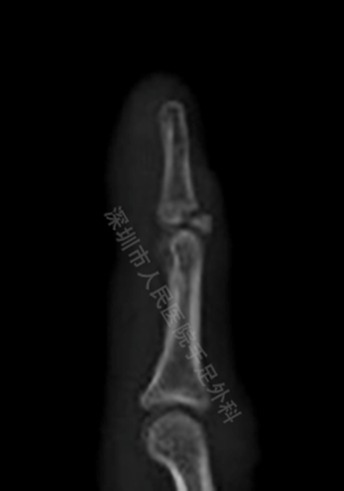

患者为陈旧性锤状指,X光片显示有撕脱骨块。